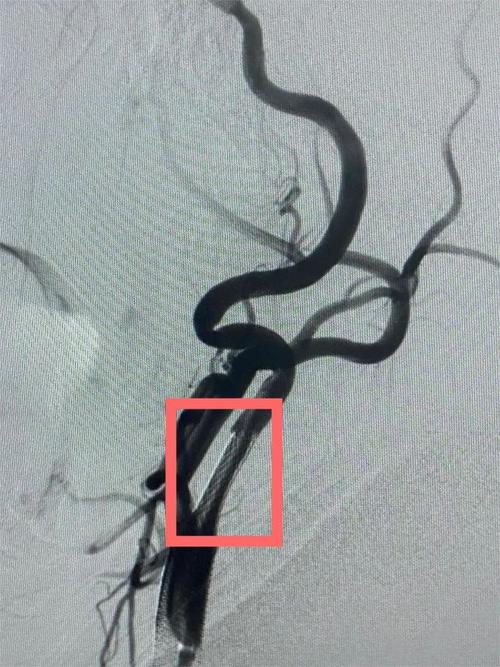

- 在X-ray(DSA)的引导下,将一根导丝小心翼翼地通过狭窄段,进入远端正常血管,作为“轨道”。

- 沿着导丝,将一个保护伞装置先送到狭窄段的远端并打开,这个“伞”的作用是捕捉在球囊扩张或支架释放过程中可能脱落的斑块碎片,防止它们再次流向大脑造成新的梗塞。

- 将一个球囊预扩张导管送到狭窄处,充盈球囊,将狭窄的血管初步撑开。

- 撤出球囊,将自膨式支架精准地放置在狭窄段,再次造影,确认支架位置良好,血管通畅,血流通畅。

- 收回保护伞,完成手术,整个过程约1小时。